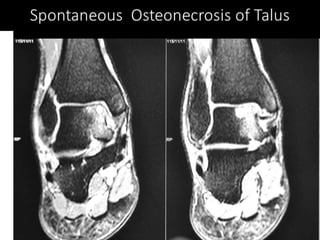

The document presents a detailed case study of a patient with transient osteoporosis of the hip (TOH) and spontaneous osteonecrosis of the knee (SONK) treated at Choithram Hospital & Research Centre in India. Over 20 years, the patient experienced multiple episodes of TOH and SONK with no history of trauma or co-morbidities, resulting in resolutions and recurrences of conditions. The information is intended for orthopedic surgery students and highlights personal experiences and case collections, with a disclaimer regarding content usage and potential controversies.